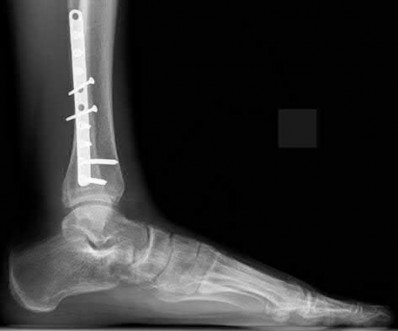

4. # After undergoing the treatment seen in Figure A, when should a patient be expected to safely operate the brakes of an automobile?

Figure A shows a patient after an open reduction and internal fixation of a bimalleolar ankle fracture.

Egol et al showed that by nine weeks, the total braking time of patients who had undergone fixation of a displaced right ankle fracture returns to the normal, baseline value.

Egol et al, also found that appropriate braking time returns at a point 6 weeks after initiation of weightbearing after treatment of lower extremity long bone and periarticular fractures, as examined with a driving simulator. No differences were seen in return of braking time between periarticular fractures and long bone injuries.